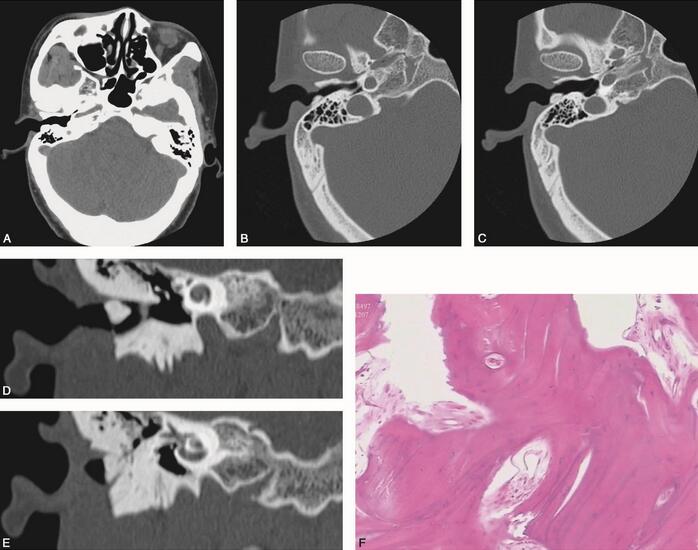

1小时条评论女,39岁,发现右耳道渐进性狭窄8个月。查体示右侧外耳道后壁明显隆起,表面光滑,未见充血和瘘管,按压无明显压痛,质硬。 【影像学表现】 于右侧骨性外耳道内可见一不规则形致密高密度隆起病灶,自外耳道后上壁向外耳道内突入(图2-2-1A),约6. 8mmtimes;2. 8mm...